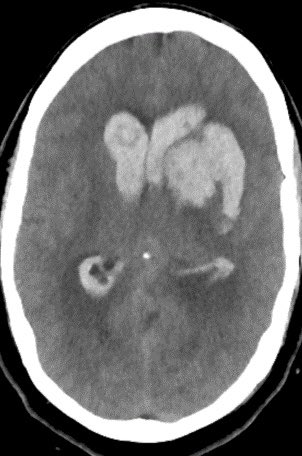

Imaging of Moyamoya disease/syndrome Imaging: Thread-like intracranial ICA/MCA with attenuated branches and “puff of smoke” appearance on DSA Co